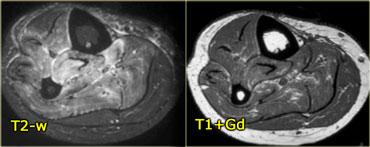

Hình bên trái là một bệnh nhân viêm cơ thể vùi.

Lưu ý tổn thương đối xứng của cơ tứ đầu đùi và sự vắng mặt của phù nề ở các tổ chức xung quanh.

Hình bên trái là một ví dụ, lưu ý các thay đổi viêm ở các cơ lớn vùng mông.

Sau khi ngừng thuốc, đau cơ sẽ biến mất trong khoảng 2 tuần, tuy nhiên MRI vẫn còn cho thấy bất thường cho đến khoảng một tháng sau đó.

Thời điểm tốt nhất để chụp MRI theo dõi là khoảng 6 tuần sau khi ngừng thuốc.

Đây là bệnh nhân cao tuổi có tăng cholesterol máu được chỉ định dùng Lipitor.

Bệnh nhân xuất hiện đau nhức cơ, CPK tăng nhẹ.

Các thay đổi khá tinh tế, chúng ta thấy các ổ tụ dịch quanh mạc cơ, ở rìa ngoài của cơ (ngoại mạc cơ).

Ngoài ra còn có thay đổi da tối thiểu.